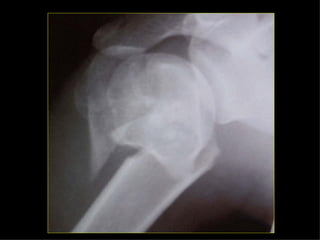

HOMBRO BRAZO CODOANTEBRAZO MUÑECA MANO Monteggia Colles Fx escafoides

HOMBRO BRAZO CODO ANTEBRAZO MUÑECA MANO Monteggia Colles Fx escafoides